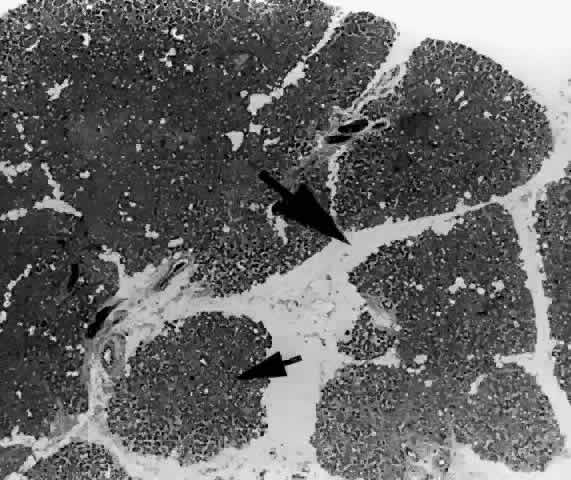

Each lobe of the lacrimal gland is separated into numerous lobules by interlobular fibrovascular connective tissue (Fig. 11). Each lobule, as seen by light microscopy, is composed of two units (Fig. 12): (1) the acinar unit (or secretory unit); and (2) the ductal system. The acinar units are further separated by intralobular fibrovascular connective tissue.

Fig. 14. Tubuloracemose architecture of the lacrimal gland. Interlobular fibrovascular connective tissue (large arrow) separates the lobules of acinar tissue (small arrow). (H & E, original magnification × 5; Courtesy of Ralph Eagle, MD, Philadelphia, PA)